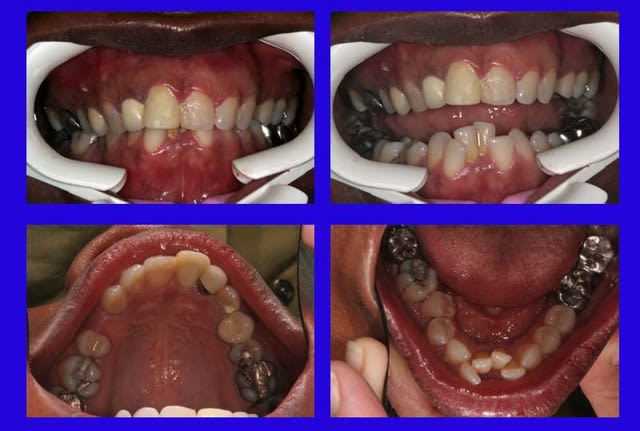

P.S.: Sexe : F.; 50 ans

Depart nvrjep - Eugenol